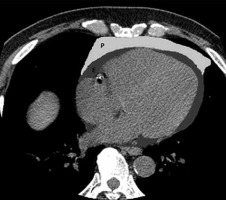

Both EAT and PAT volumes from CT images were quantified using Image J software [9]. All CT slices along the entire cardiac region, which included EAT and PAT, were manually segmented after setting a threshold of –200 to –30 Hounsfield units (HU) using the threshold plugin. A wand tracing tool was used to highlight the EAT and PAT, as shown in Figure 1. Finally, the measure tool was used to obtain the area of each adipose tissue. The final volume was calculated from the sum of the areas of all slices multiplied by the slice thickness and spacing between slices.